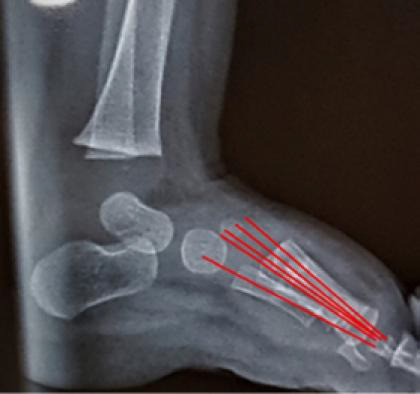

Results: Data from thirty articles included in this review were arranged into different subheadings. In the anteroposterior view (AP), assessment of the hindfoot deviation was by the AP talo-calcaneal angle (Kite's angle); the forefoot and midfoot for abduction and adduction alignment was by the AP talo-first metatarsal angle, the talo-second metatarsal angle, the calcaneo-second metatarsal angle, the calcaneofifth metatarsal angle; the forefoot and midfoot rotation was by observing the normal proximal convergence of the metatarsal bones axes. In the lateral view, assessment of the hindfoot sagittal plane alignment was by the lateral tibio-calcaneal angle; hindfoot varus or valgus deviation by the lateral talo-calcaneal angle; talus bone alignment by talar declination angle and the tibio-talar angle; calcaneal bone alignment by the calcaneal inclination angle and the tibio-calcaneal angle, the midfoot and forefoot sagittal plane alignment for the plantar arch by the lateral talo-first metatarsal -Meary's- angle, the calcaneal inclination angle, and the lateral calcaneofirst metatarsal -Hibbs- angle; forefoot and midfoot rotational alignment by observing the overlap shadows of the metatarsals' shafts and drawing their axes.

Conclusion: Drawing certain lines and angles with a systematic approach to assess different regions of the foot in the radiographic films of children can facilitate the process of assessment of the foot (as a whole) for deformities.